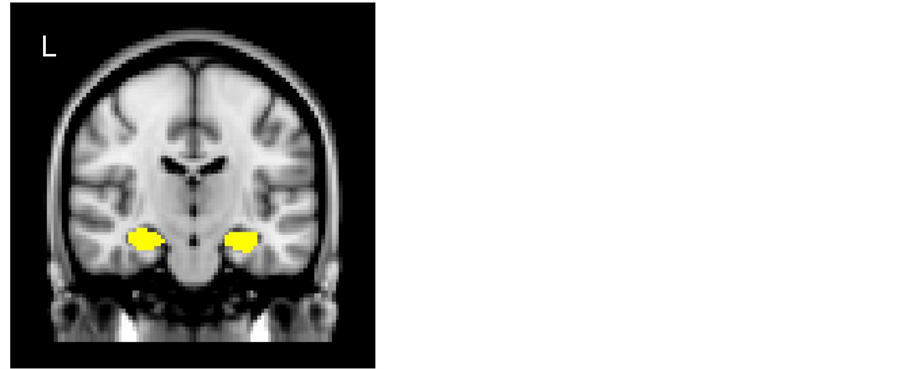

For measurements of GM volumes in the left and right HPCs in each subject, T1-weighted volumetric images were analyzed using SPM8 (Wellcome Department of Cognitive Neurology, London, UK) implemented in Matlab 2015a (MathWorks, Natick, MA, USA) to carry out VBM8 (http://dbm.neuro.uni-jena.de/vbm8/) using default parameters. Each image was inspected for reconstruction artifacts. The VBM8 method combines spatial normalization, segmentation, and volumetric modulation. The toolbox employs a hidden Markov random field (HMRF) model in the procedure to segment each image into GM, white matter, and cerebrospinal fluid. The toolbox then normalizes the GM segment of each image to the International Consortium for Brain Mapping (ICBM) 152 template (Montreal Neurological Institute; MNI) and performs a modulation step to scale each voxel value according to the subject’s total intracranial volume, as well as the regional GM volume expansion/contraction that occurs during nonlinear transformation. The aim of the modulation step was to render the final VBM statistical data reflective of the “volume” change rather than the “concentration” change in GM. GM image segments were inspected for segmentation artifacts, then smoothed using an isotropic Gaussian kernel of 12 mm full width at half maximum (FWHM), to accommodate individual differences in the sulcal and gyral anatomy, and to meet the distributional assumptions of the general linear models necessary for statistical analysis. An absolute threshold mask of 0.10 was used to avoid possible edge effects around the border between GM and the white matter. Finally, we determined the GM volumes in the left and right HPCs, respectively, as follows: the mean signal intensities on T1-weighted images were extracted from the left or right HPC using the Harvard-Oxford Subcortical Structural Atlas from Version 6.0, which is part of the FMRIB’s Software Library (FSL, http://www.fmrib.ox.ac.uk/fsl), using a probability threshold mask of 60 (Figure 1). In addition, the left and right cerebral hemispheres were also estimated as control ROIs, using the atlas of AAL (http://www.gin.cnrs.fr/AAL).

Figure 1. ROI masks (yellow) of left and right hippocampi (HPCs) determined on the basis of Harvard-Oxford Subcortical Structural Atlas.